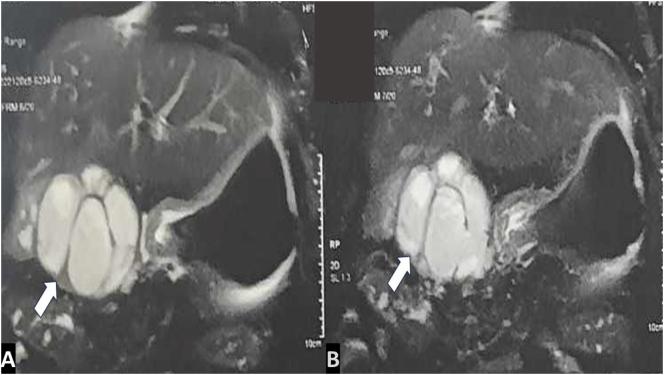

A 70-year-old patient presented with right hypochondrial pain and a palpable gallbladder. A CT scan revealed a distended lithiasic gallbladder with a thickened irregular wall and hepatic nodules. A hepatic MRI suggested xanthogranulomatous cholecystitis. A CT-guided biopsy of the liver nodule showed no signs of malignancy. An open cholecystectomy with a trans-cystic drain was performed. Histological examination confirmed chronic xanthogranulomatous cholecystitis. The patient was discharged on postoperative day 10. A clinical and radiological follow-up at 6 months postoperatively showed no abnormalities.